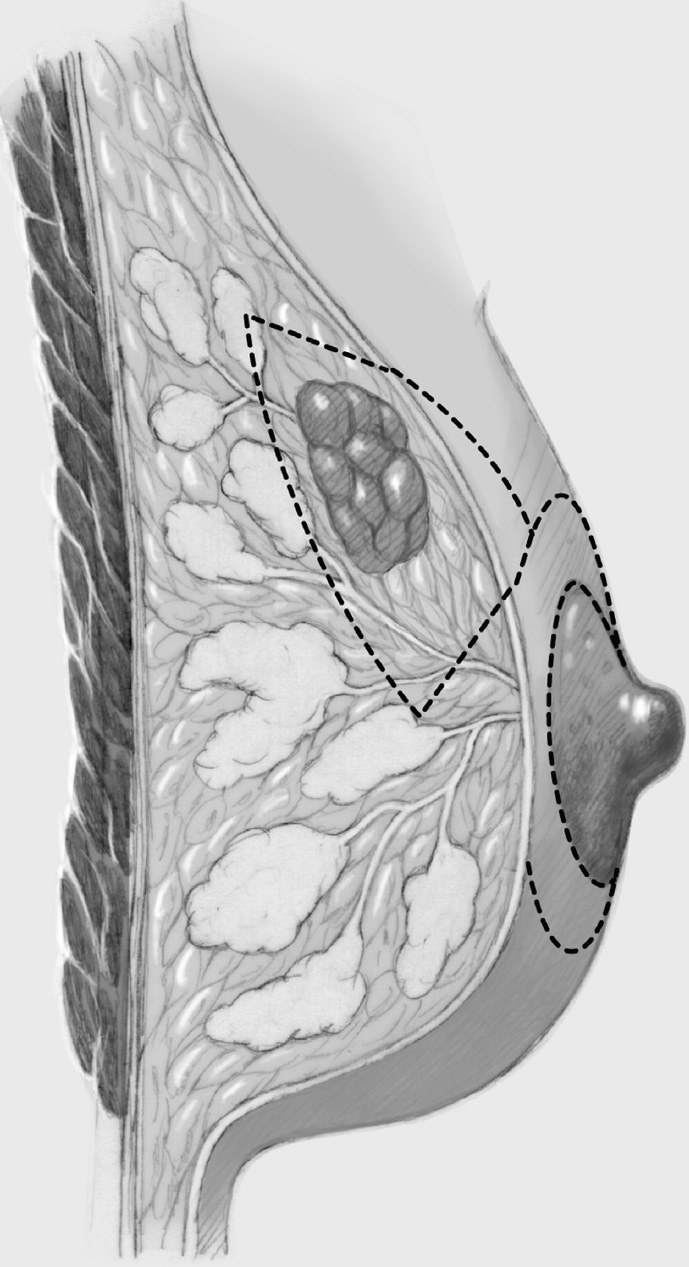

The various intramammary pedicles and different incisions for appropriate reduction of the overlying skin are shown in the chapter on reduction mammoplasty (Chapter 3.3.2). The classic modern pedicles (inferior central, superior, and purely central) with the corresponding incisions (inverted T, short inferior incision [vertical periareolar], and periareolar) are presented below.

Inferior Central (Central Caudal) Pedicle with Inverted T Incision

Among reduction mammoplasties, this technique is regarded as relatively low-risk and is therefore suitable also in smokers and older postmenopausal patients (impaired perfusion). Because the breast volume may be reduced by more than 50%, the method can also be used when the breasts are very large. The approach is suitable especially for tumors in the upper quadrants, central tumors, and tumors in the upper part of the lower quadrants.

Following the skin incision, the superior skin envelope is dissected off the breast, that is, in a superior, medial, and lateral direction. This step is crucial as it provides maximum access to the breast, enabling reduction to be “tailored” exactly to the tumor.

The breast containing the tumor is resected in classic segmental fashion along the tumor axis. In purely cosmetic reduction, tissue is removed mainly in the upper outer part and somewhat less in the superior and medial part. It is important to leave sufficient breast tissue behind the areola and in the cranial part as otherwise the projection of the areolar region will be poor after it is sutured. Additional tissue can be resected lateral to the inferior pedicle on right and left.

Inferior and central posterior breast tissue is mainly resected. As in all tumor-adapted procedures, dissection continues down to the pectoralis major muscle, elevating the residual breast in the superior direction. The final step is “retrograde” resection in the upper part of the breast also, which is important for the final shape of the breast. Nevertheless, the technique is not the first choice when the tumor is located in the upper quadrants.